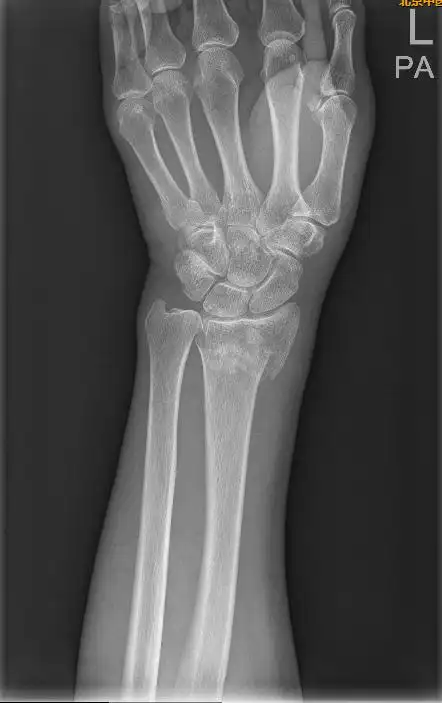

【手法整复】桡骨远端骨折_桡骨下端骨折_桡骨下端骨折康复锻炼 - 好